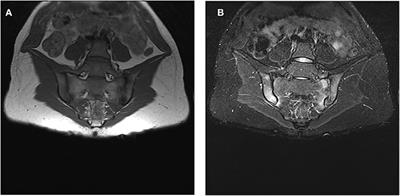

List of Radiology thesis topics /Radiology dissertation topics /research paper topics in radiology for reference / DNB radiology thesis topics / MD radiology thesis topics : State of the art of MRI in the diagnosis of hepatic focal lesions . Multimodality imaging evaluation of sacroiliitis in newly diagnosed patients of spondyloarthropathy . Tirads Calculator β§ Frcr Exam